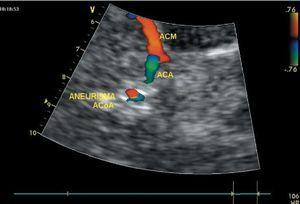

Figura 2. Imagen circular típica de aneurisma cerebral. En modo color se identifican doble color con línea separadora con ausencia del mismo. ACM: arteria cerebral media; ACA: arteria cerebral anterior; ACoA: arteria comunicante anterior.

Hemorragia subaracnoideaLos aneurismas se reconocen con el DTCC en modo color por la presencia de una formación circular u ovalada adyacente a un vaso, y en cuyo interior el flujo está dividido en dos zonas, una azul y la otra roja con una zona intermedia de flujo cero y sin turbulencias (fig. 2). Aneurismas mayores de 5 mm y no trombosados pueden localizarse en un 47-85% de las ocasiones, dependiendo su visualización del tamaño, de la localización y de la morfología del aneurisma50,51, mejorando los resultados con la utilización de ecopotenciadores52. Con la reconstrucción tridimensional (3D), el porcentaje de aneurismas diagnosticados llega al 97%53. De todos modos, el DTCC no parece aún la técnica idónea para descartar la presencia de un aneurisma54 aunque es útil en el seguimiento posembolización de estos enfermos, especialmente en la comprobación de la ausencia de flujo dentro del aneurisma o en su reaparición en caso de recanalizaciones espontáneas55,56 y descartando los posibles desplazamientos de los coils57.